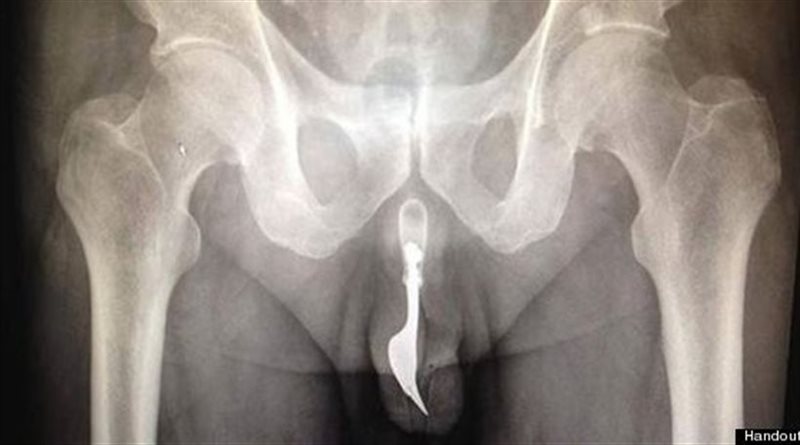

ΗΜΑΡΤΟΝ! 70χρονος έβαλε ένα πιρούνι στο πέος του!!

Αν είναι δυνατόν....Τελικά το ανθρώπινο μυαλό δεν έχει αναστολές! Δέκα εκατοστών πιρούνι κατάφεραν να αφαιρέσουν οι γιατροί στο νοσοκομείο της Καμπέρα στην Αυστραλία από το... πέος ενός 70χρονου άνδρα.

Όπως έγινε γνωστό, ο συνταξιούχος βρέθηκε μόνος του σε αυτή την δύσκολη θέση αφού τοποθέτησε το πιρούνι μέσα στην ουρήθρα του προκειμένου να νιώσει την απόλυτη ηδονή!

Οι γιατροί οι οποίοι εγχείρησαν τον άνδρα μίλησαν για το παράξενο αυτό περιστατικό σε συνέντευξή τους στο περιοδικό Χειρουργικής International Journal of Surgery Case Report.

Όπως είπαν, κατάφεραν να αφαιρέσουν το μαχαιροπίρουνο από το μόριο του 70χρονου χρησιμοποιώντας μεγάλη ποσότητα λιπαντικού και λαβίδες, ενώ σχολιάζοντας την απόφαση του ηλικιωμένου παραδέχθηκαν πως το ανθρώπινο μυαλό δεν έχει αναστολές.